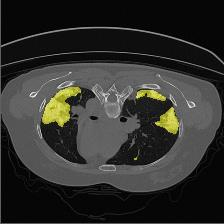

Medical image segmentation is one of the most fundamental tasks concerning medical information analysis. Various solutions have been proposed so far, including many deep learning-based techniques, such as U-Net, FC-DenseNet, etc. However, high-precision medical image segmentation remains a highly challenging task due to the existence of inherent magnification and distortion in medical images as well as the presence of lesions with similar density to normal tissues. In this paper, we propose TFCNs (Transformers for Fully Convolutional denseNets) to tackle the problem by introducing ResLinear-Transformer (RL-Transformer) and Convolutional Linear Attention Block (CLAB) to FC-DenseNet. TFCNs is not only able to utilize more latent information from the CT images for feature extraction, but also can capture and disseminate semantic features and filter non-semantic features more effectively through the CLAB module. Our experimental results show that TFCNs can achieve state-of-the-art performance with dice scores of 83.72\% on the Synapse dataset. In addition, we evaluate the robustness of TFCNs for lesion area effects on the COVID-19 public datasets. The Python code will be made publicly available on https://github.com/HUANGLIZI/TFCNs.